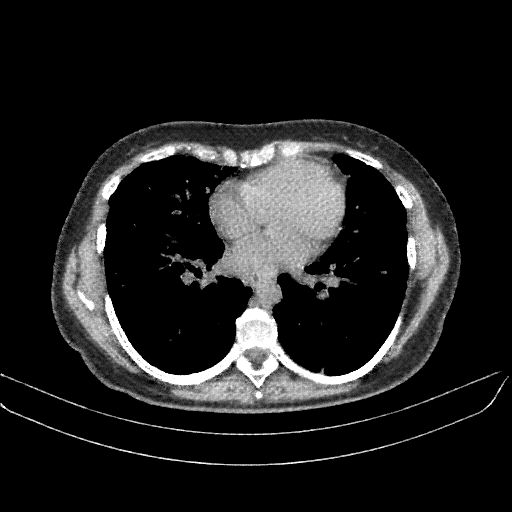

Targeted Slice 70 - Mediastinum Window Analysis (Generated vs Real Venous)

0.759

Mediastinum SSIM

45.2

Mediastinum RMSE

16.1

Mediastinum MAE

Average Mediastinum Window Metrics Across All Slices (133 slices) - Generated vs Real Venous

0.736

Mediastinum SSIM (Avg)

46.4

Mediastinum RMSE (Avg)

17.0

Mediastinum MAE (Avg)

Mediastinum window (WL 40, WW 400 β†’ Low βˆ’160, High +240)